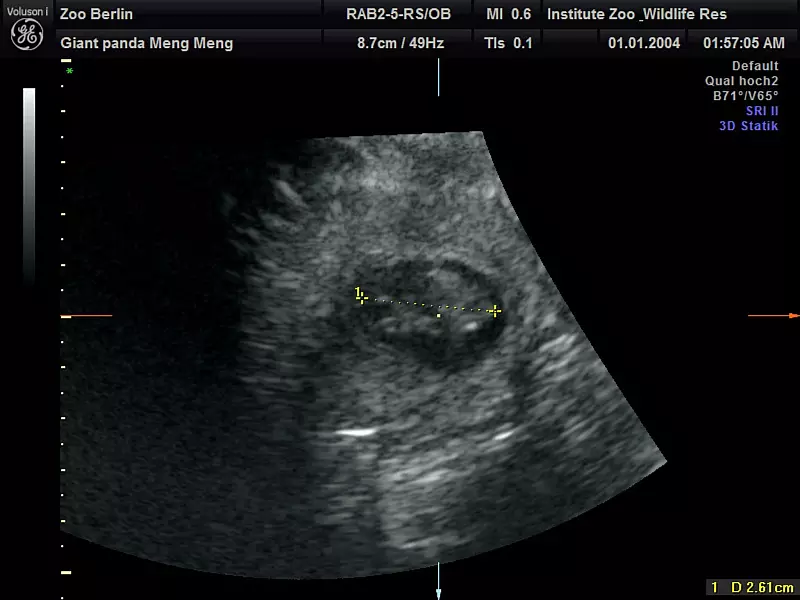

Im Berliner Zoo wird wieder Panda-Nachwuchs erwartet. «Die Babys sind etwa 2,5 Zentimeter groß und müssen jetzt bis zur Geburt noch ordentlich wachsen», sagte Thomas Hildebrandt, Leiter der Abteilung für Reproduktionsmanagement am Leibniz-Institut für Zoo- und Wildtierforschung laut Pressemitteilung. Im Panda Garden sei am Sonntag ein kleiner Jubel ausgebrochen, teilte der Zoo mit. Die Panda-Dame hatte sich zuletzt nicht besonders kooperativ gezeigt. «Trotz sichtlichen Bauchkneifens» habe Meng Meng sich aber überzeugen lassen, «in den aufrechten Stand zu kommen und das kühle Ultraschall-Gel sowie die Untersuchung mit der Ultraschall-Sonde zu akzeptieren», sagte der Veterinärmediziner, der als internationaler Experte bei der Reproduktion von Großen Pandas gilt. «Eine Untersuchung im Stehen hat schließlich die freudige Nachricht gebracht, dass Meng Meng mit zwei Jungtieren trächtig ist.»

Die Babies sind etwa 2,5 Zentimeter groß. (Handout) - © Zoo Berlin/dpa

Die Babies sind etwa 2,5 Zentimeter groß. (Handout) (© Zoo Berlin/dpa)